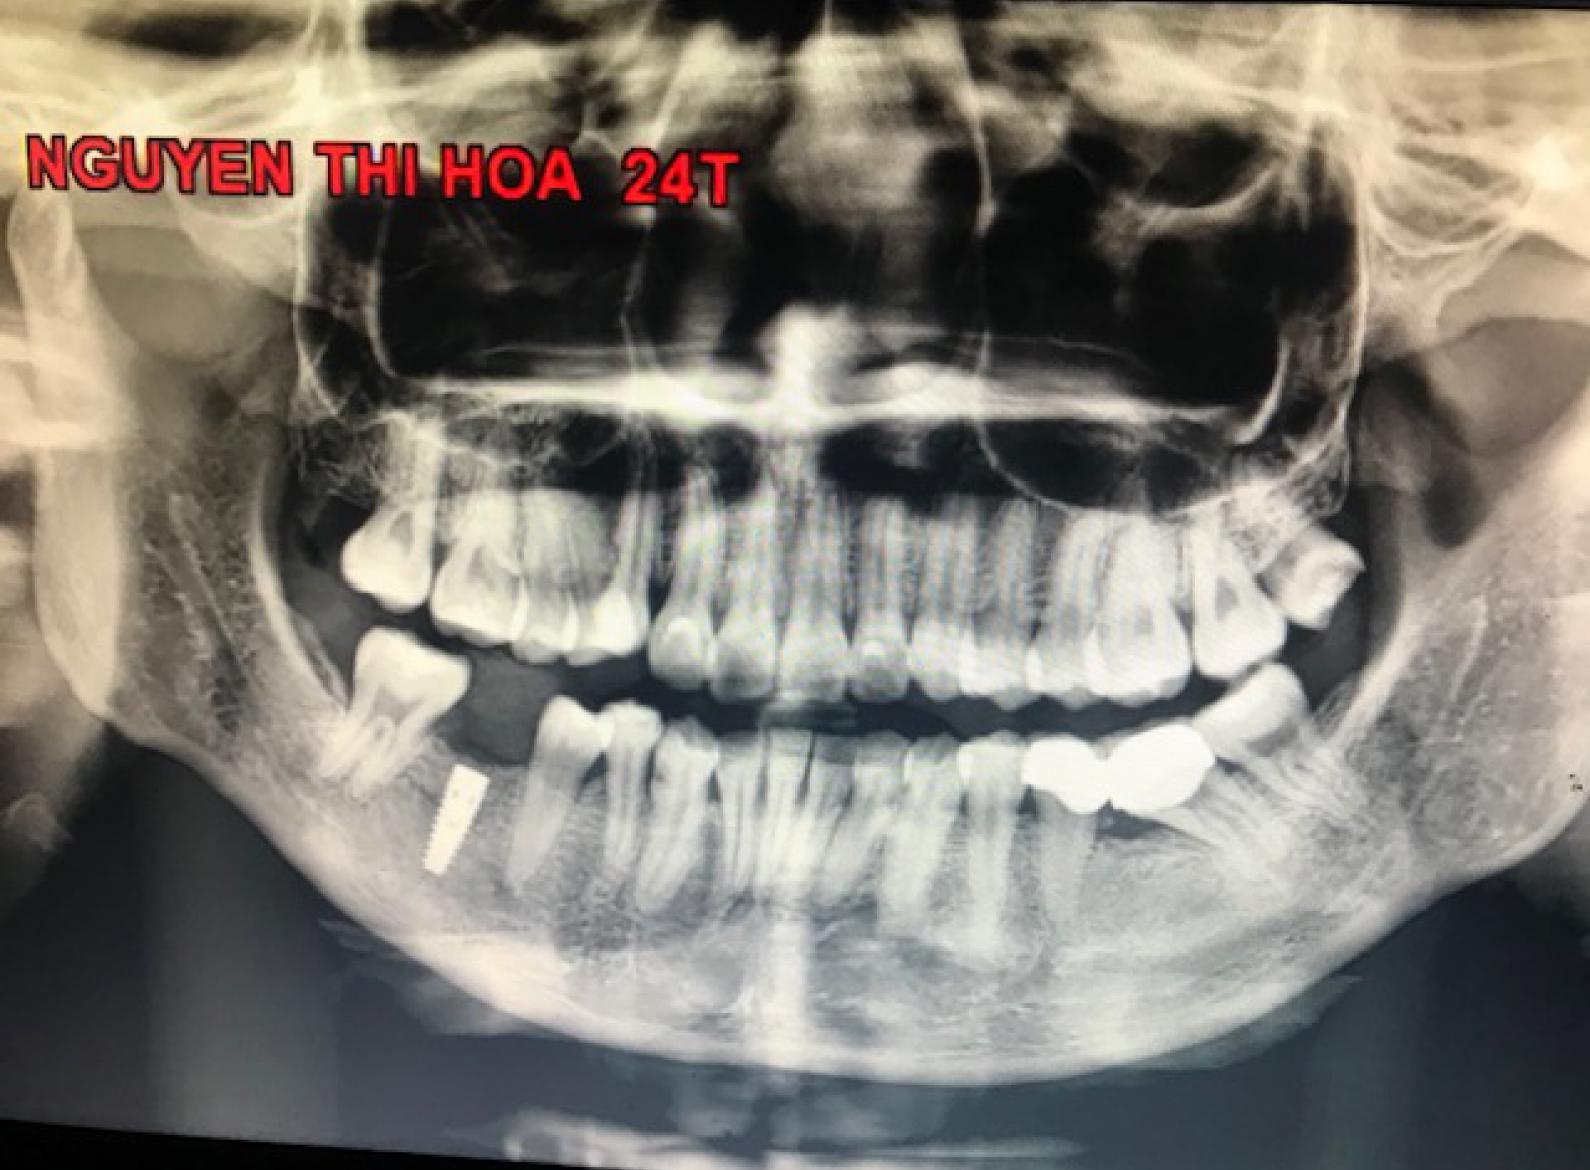

Cấy răng tốt nhất là cấy răng có chỉ định đúng nhất, nếu chỉ định chặt quá sẽ bị hạn chế cho kỹ thuật, nếu chỉ định rộng quá sẽ có tỷ lệ thất bại cao.